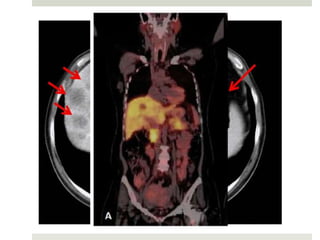

 Los exámenes que recomienda la NCCN:

 Exámenes de rutina.

 Endoscopia.

 TC de Tórax y Abdomen con doble contraste.

 Valorar metástasis.

 Se solicita PET en caso de evidencia de metástasis.